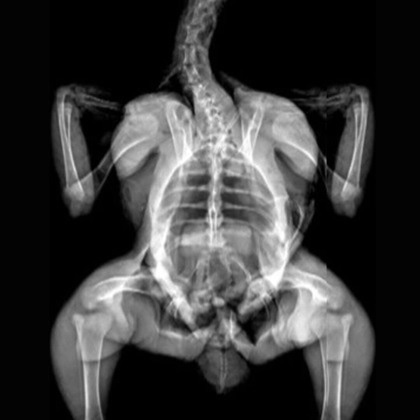

X-Ray Attenuation Image - Rat. Image Credit: Scintica Instrumentation Inc

Bone Mineral Density Image - Rat. Image Credit: Scintica Instrumentation Inc